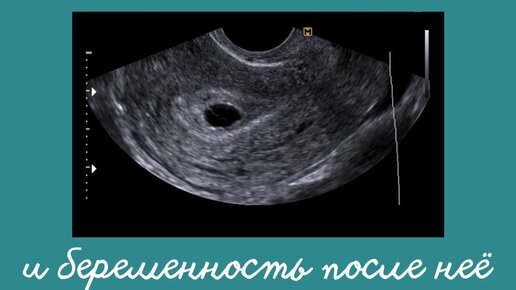

Анэмбриония и беременность после нее

Анэмбриония — даже по названию можно догадаться: речь об отсутствии эмбриона внутри плодного яйца. Куда он мог деться? Эмбрион или вообще не сформировался, или на самых ранних стадиях остановился в развитии. Где искать причину? Честно говоря, чаще всего это просто случайность. Генетическая поломка, от которой никто не застрахован. Но имеют большое значение инфекции, воспалительный процесс. Могут влиять токсические вещества, лекарства, гормональные нарушения, употребление алкоголя и табака. Симптомов у анэмбрионии вовсе нет...

Анэмбриония — одно из нарушений нормального развития беременности, при котором в плодном яйце нет эмбриона. Поэтому состояние еще называют синдромом пустого плодного яйца. Причины анэмбрионии На это могут повлиять нарушение функции щитовидной железы, острые вирусные и бактериальные инфекции, морфологические и хромосомные аномалии эмбриона, генетические «поломки», факторы образа жизни. Причины насколько многообразны, что не всегда ясны точно. Что происходит дальше Тест на беременность и анализ на ХГЧ сначала показывают положительный результат, поэтому кажется, что все идет хорошо...